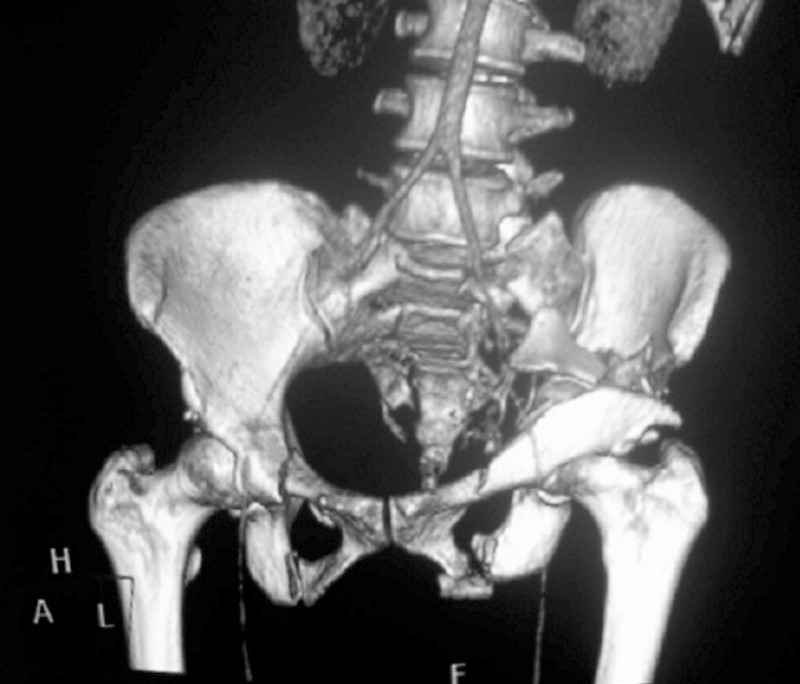

This complex and displaced sacral injury is likely an H pattern...2 hemipelvic components, an upper sacral component which remains attached to the lumbar spine, and a caudal sacral component...there are typically anterior ring injuries as well...in this patient's example, the left sided acetabulum also has been exploded.

Fixation stability can be reliably achieved for simpler and less displaced or less comminuted fractures using transiliac-transsacral screws...for most adults, these are usually 170-190mm lengths through the upper sacral segment after reduction.

For those patterns with the transverse limb below the second sacral segment level, second sacral segment transiliac-transsacarl screws can also be used...these screws are usually 150-160 mm lengths.

For this patient (according to the limited imaging available), it would seem that a combination of lumbo-pelvic fixation along with transiliac transsacral fixation is optimal...BUT the left sided pelvic implants must be applied in consideration of and in anticipation of the necessary acetabular fixation implants.

So you are correct, this pattern likely needs a great reduction and a powerful fixation construct to be durable...but the operative exposure and implants must be planned carefully if the acetabular fracture is to be accurately reduced and well stabilized.